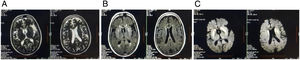

She had no history of addiction and no family history of any neurological disorders. Brain MRI revealed symmetrical hyperintense signals in T2-weighted imaging, T2-FLAIR and DWI over bilateral caudate nucleus and putamen (Fig. 1). Clinical–radiological differential diagnoses that were considered are shown in Table 1. Eventually, she was diagnosed to be a case of an extrapontine variant of osmotic demyelination syndrome (ODS) due to HHS, which was precipitated by COVID-19, that in turn had been treated with dexamethasone.